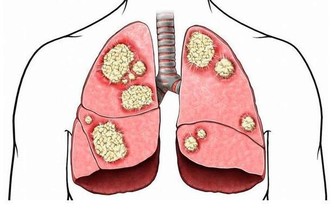

所以我們在平時就要時刻關注自己的情緒,增強情緒的免疫力,人生最大的痛苦都來自情緒,情緒之傷往往最容易被人所忽略,過去的情緒:後悔愧疚悲傷怨恨憂傷自責憤怒,未來的情緒:不安焦慮緊張自卑害怕驚恐,情緒會被壓制進入潛意識形成仇恨跟痛苦,長期積累導致肝鬱氣滯最後顯化成為疾病,諸如躁鬱/社交恐懼症/驚恐症/暴食/抑鬱症/強迫症/上癮/乳腺增生/雙向情感障礙(心境障礙)/木僵/自閉症/妄想等。